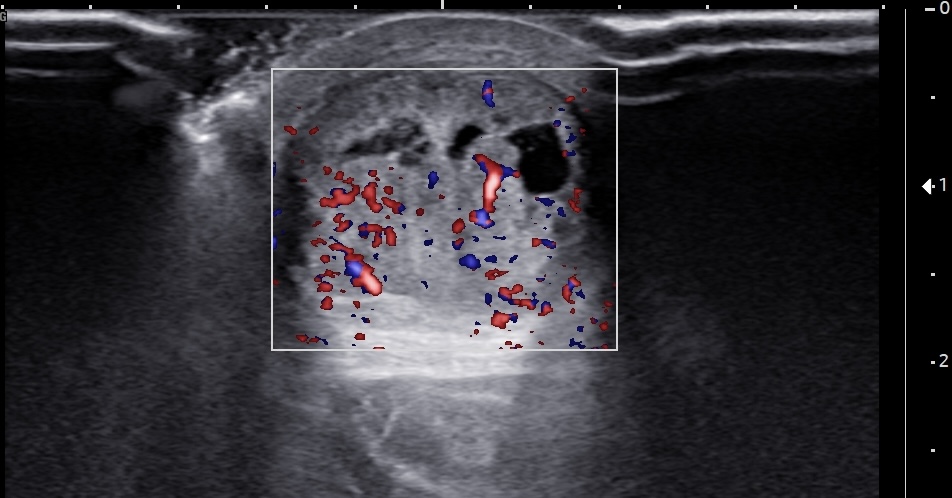

Unlabeled short-axis ultrasound image of the midportion Achilles tendon using color Doppler, demonstrating multiple intratendinous neovessels consistent with chronic and severe tendinopathy.